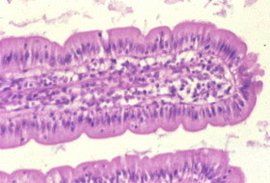

腸絨毛

腸絨毛是一個生物學名詞,是小腸的上皮和固有層向腸腔隆起形成很多指狀突起。

小腸

隆起,形成很多指狀突起,稱為腸絨毛。

包含和作用

內含有

養料

的作用。